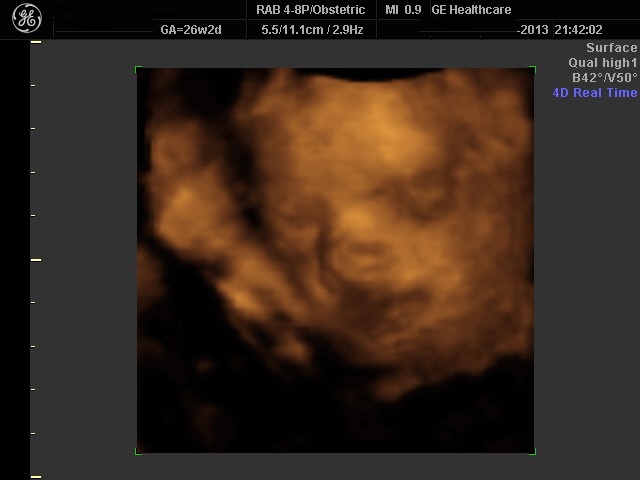

Είναι μία εντυπωσιακή απεικόνιση του εμβρύου μέσα στο "δικό του χώρο". Υπάρχει η δυνατότητα στατικής απεικόνισης όσο και "realtime".Τα αποτελέσματα απεικονίζονται σε ψηφιακή μορφή και αποτελούν επί της ουσίας τη πρώτη οπτική επαφή του ζευγαριού με το έμβρυο.

Στην πραγματικότητα η χρήση του είναι να επιβεβαιώσει μία ανωμαλία η οποία ανιχνεύεται με τη δισδιάστατη υπερηχογραφία.